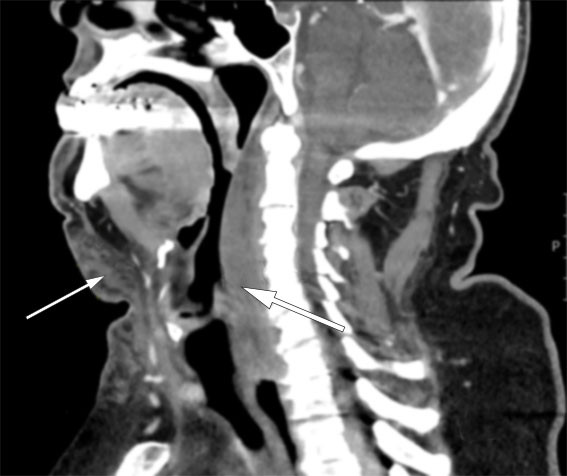

CT collum med intravenøs kontrast ble utført for å se etter blødningskilde, utbredelse av hematom og eventuelle underliggende funn. Undersøkelsen påviste ingen pågående blødning eller pseudoaneurisme. Hematomet var diffust avgrenset i bløtdelene og strakk seg fra os hyoideum til trakea og glandula thyreoidea samt retrofaryngealt med ledsagende lett innbukning i farynks dorsalt, svarende til C2–C7-nivå (figur 1).

CT collum viste at hematomet strakk seg retrofaryngealt, uten at dette var synlig i slimhinnen i farynks. I litteraturen er det beskrevet både akutt intubasjon og akutt trakeotomi for å sikre åpne luftveier hos denne pasientgruppen (3, 4). Dette ble ikke funnet nødvendig, da respiratoriske parametere var upåfallende. Pasienten hadde heller ikke stridor og var våken og orientert.